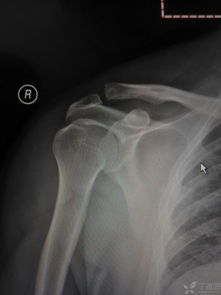

1.保守療法Ⅰ型肩鎖關(guān)節(jié)脫位者,休息并用三角巾懸吊1~2周即可;Ⅱ型脫位者,可采用背帶固定。方法為患者立位,兩上肢高舉,先上石膏圍腰,上緣齊乳頭平面,下緣至髂前上棘稍下部,圍腰前后各裝一鐵扣,待石膏干透后,用厚氈一塊置鎖骨外端隆起部(勿放肩峰上),另用寬3~5cm皮帶式帆布帶,越過患肩放置的厚氈,將帶之兩端系于石膏圍腰前后的鐵扣上,適當(dāng)用力拴緊,使分離之鎖骨外側(cè)端壓迫復(fù)位(圖2)。拍片證實(shí)復(fù)位,用三角巾兜起傷肢,固定4~6周。亦可在局麻下復(fù)位,從鎖骨遠(yuǎn)端經(jīng)肩鎖關(guān)節(jié)與肩峰作克氏針交叉固定。術(shù)后懸吊患肢,6周后拔出鋼針,行肩關(guān)節(jié)功能鍛煉。

(1)肩鎖關(guān)節(jié)切開復(fù)位克氏針固定術(shù):此法適用于Ⅱ型脫位病例。病人取仰臥位,患肩墊高,常規(guī)消毒、鋪巾,頸路肌間溝麻醉生效后,沿鎖骨外端并繞過肩峰做切口,長約8~9cm(圖4),骨膜下將斜方肌和三角肌附著處切開分離,顯露肩鎖關(guān)節(jié),清除碎骨片及關(guān)節(jié)間組織,將上臂向上推,并同時(shí)向下壓鎖骨外端,使肩鎖關(guān)節(jié)復(fù)位,兩枚克氏針交叉穿過肩鎖關(guān)節(jié)固定;修復(fù)肩鎖韌帶、關(guān)節(jié)囊和喙肩韌帶,剪除多余的克氏針,將遠(yuǎn)端彎成鉤狀埋入皮下,以防克氏針發(fā)生移位、滑脫,再將斜方肌和三角肌邊緣在鎖骨及肩峰處褥式縫合,最后縫合皮膚,術(shù)后用三角巾懸吊傷肢4~6周。

如用此方法治療Ⅲ型肩鎖關(guān)節(jié)脫位,應(yīng)在上述操作的同時(shí),經(jīng)鎖骨至喙突加1枚螺絲釘固定,使兩骨靠近,以利喙鎖韌帶修復(fù)。術(shù)后4~6周拔除鋼針,1年后取出螺絲釘(圖5)。